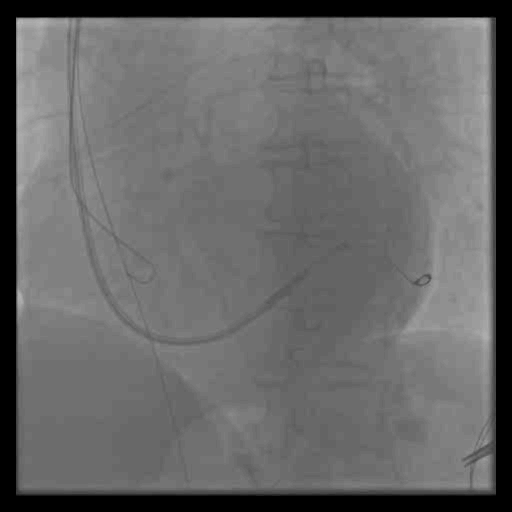

病例二

Finecross微导管,runthrough,pilot150,conquest Pro,RG3导丝 2.5*20球囊

手术过程